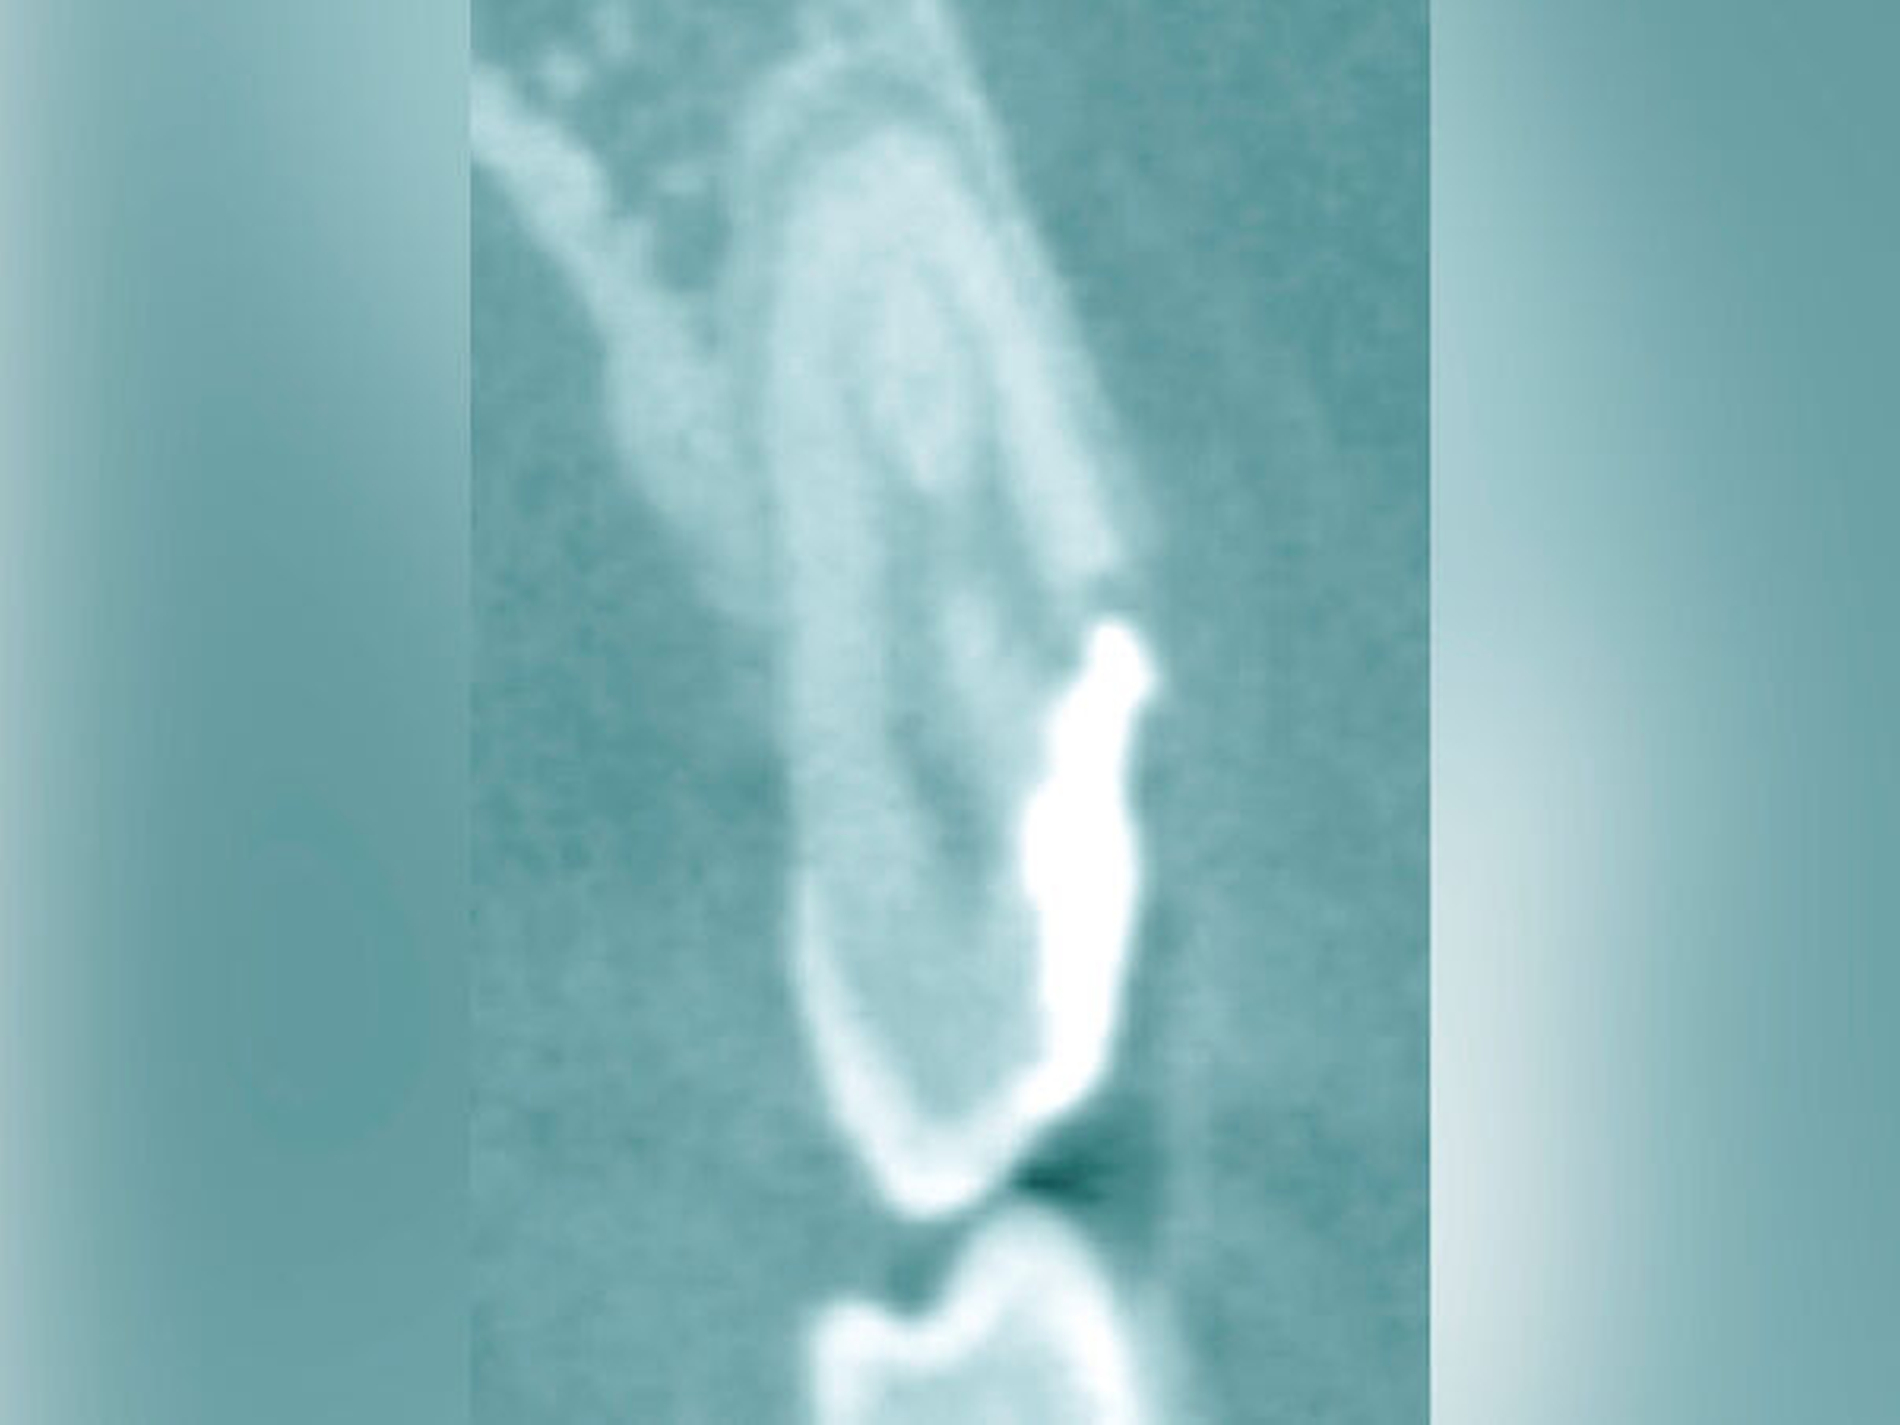

Eine weitere Möglichkeit, tief zerstörte Zähne möglichst schonend chirurgisch zu extrudieren, basiert auf axialen Zugsystemen (Abbildungen 2 bis 4). Diese erscheinen vorteilhaft bei sehr schwierigen Fällen, zum Beispiel bei Zähnen mit fehlendem Ansatzpunkt für die Zange sowie bei langen oder sehr ovalen Wurzeln. Axiale Zugsysteme ermöglichen die Übertragung von Zugkräften auf die Zahnwurzel, ohne die Alveole unnötig zu dehnen. Dazu wird eine spezielle Schraube in den Wurzelkanal eingebracht und das Gewinde der Schraube für eine ausreichende Friktion fingerfest eingedreht. An diese Schraube wird ein gerätespezifisches Zugsystem angelegt. Durch rein axial wirkende Zugkräfte werden traumatische Effekte auf Knochen und Wurzeloberfläche während der Zahnmobilisation minimiert. Gegebenenfalls können feine Luxatoren vorsichtig unterstützend eingesetzt werden. Im Tiermodell wurde an extrahierten und wieder replantierten Zähnen mit ovalem Querschnitt gezeigt, dass der Verlust von Zementoblasten auf der Wurzeloberfläche geringer ist, wenn ein axiales Zugsystem anstatt einer Extraktionszange verwendet wird.

Die wesentliche technische Komplikation stellt das unverhältnismäßige Erweitern des Wurzelkanals für die Retention des Zughilfsmittels – zum Beispiel der Benex-Schraube – dar. Der Behandler sollte hier unter besonderer Vorsicht den bereits instrumentierten und präparierten (vorgegebenen) Wurzelkanal als Bohr- und Zugpfad für die Extrusion nutzen. Auf die Schonung der gesunden Zahnhartsubstanz muss geachtet werden. Die Bohrachse für die Ausrichtung der Zugschraube muss mit dem koronal gelegenen Hauptpfad des Wurzelkanals übereinstimmen. Zudem ist für das Erzielen einer ausreichenden Retention der Schraube ein gewisses Maß an Feingefühl und Taktilität vom Behandler erforderlich. Eine neue Schraube erfüllt die Vorbedingung eines schneidfreudigen Gewindes und damit eines guten Halts im Zahn am besten.